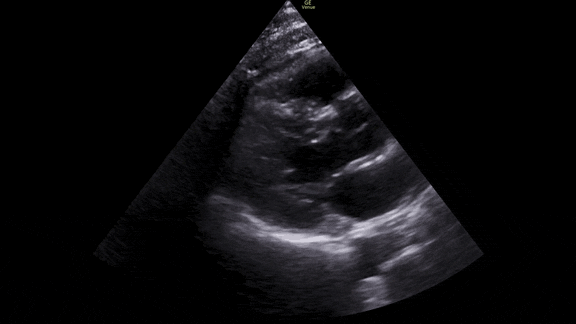

First we get a parasternal long axis view:

We must be able to identify the structures in the image: